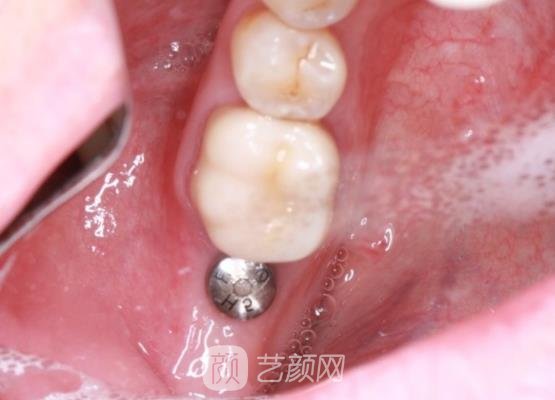

医生在确认我的身体没有一些特殊的情况下,帮我制定了适合我的种植牙材质和手术方案,接下来就开始了手术,手术过程中因为采用了麻药的处理,所以我也没有感觉到很剧烈的疼痛感。

短短几个小时手术就结束了,刚结束时我的牙龈处还存在着一些肿胀的情况,还有一些疼痛的感觉,医生告诉我过几天这些现象就会消失,让我不用太过于的担心,如果几天后牙龈处还有痛感,让我及时的与他联系进行复查。

几个月后我一直按照医生的话,对待饮食方面总是很注意,虽然过程是比较难熬的,但是现在我的牙齿已经恢复的很自然了,而且口腔里面也没有异物的感觉,所以我还是觉得这些天的努力都是值得的,现在我的牙齿问题终于得到解决了。